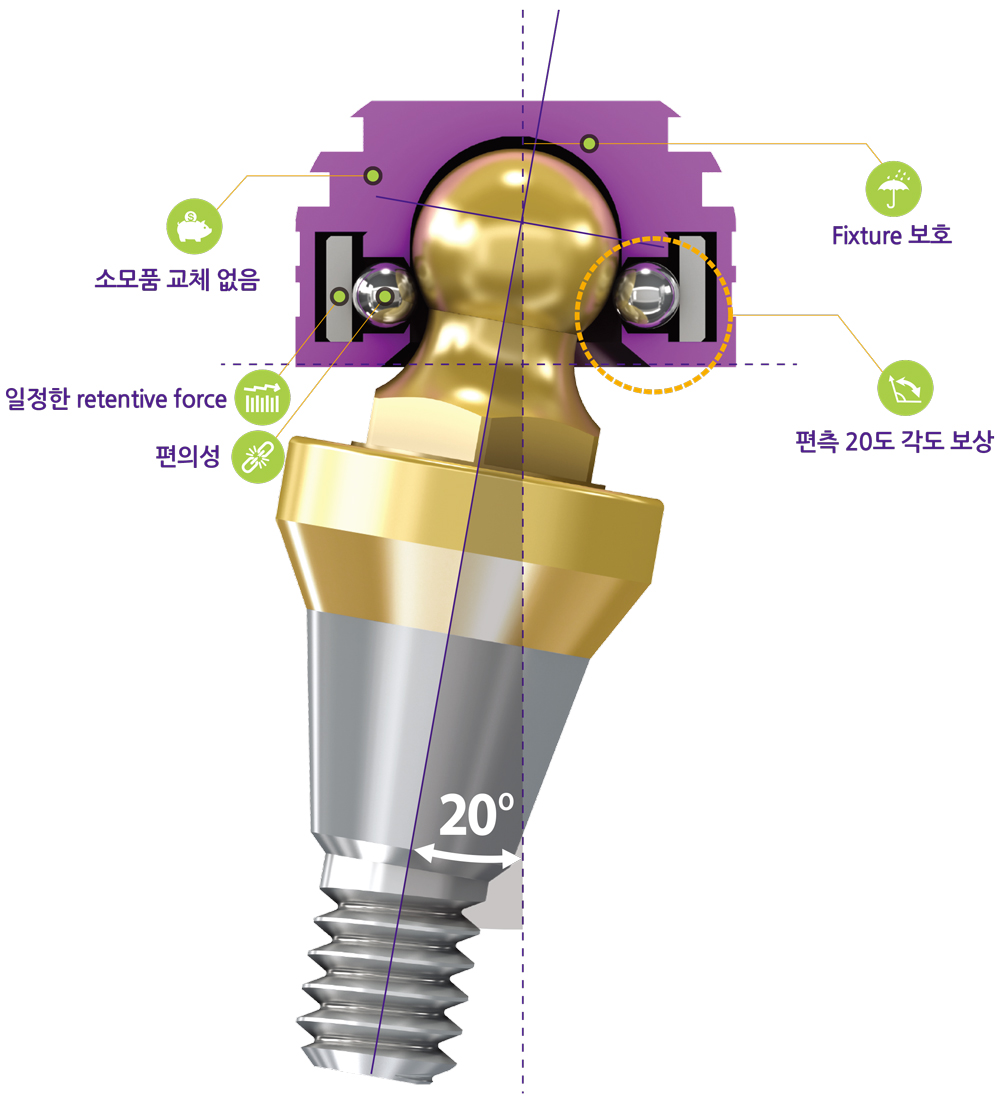

부분 상세설명 소모품교체 없음

소모품교체 없음Titanium housing과 Zirconia ball, Nitinol pan spring으로 이루어져 있어 소모품 교체 없이 장기간 사용이 가능하다.

일정한 retentive force

일정한 retentive force약 20,000회의 탈부착 시에도 retentive force가 감소하지 않고 일정하게 유지한다

편의성

편의성Denture 장착 시 ‘딸깍’ 소리가 나기 때문에 정확한 장착 여부를 쉽게 인지할 수 있다.

Fixture 보호

Fixture 보호Locking 시 지대주와 housing 사이에 0.8mm 가량의 공간이 부여되어 의치 기능 시 연조직의 위축량을 보상함으로써 지대주에 가해지는 힘을 줄일 수 있다.

편측 20도 각도 보상

편측 20도 각도 보상지대주의 groove와 housing ball & spring이 체결되는 ‘EZ LOCKING 방식’에 의해 fixture의 식립각도를 20도까지 보상할 수 있다. (각도별 housing positioner 이용)